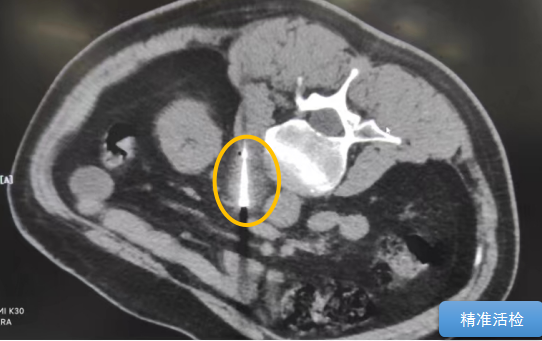

經(jīng)過多學(xué)科討論,陳寶瑩主任根據(jù)影像資料指出,患者轉(zhuǎn)移瘤位于腹膜后,內(nèi)側(cè)瀕臨人體最大的血管——主動(dòng)脈;前方同樣有血管緊貼腫瘤;外側(cè)是腎臟,后方是椎體和神經(jīng),夾縫中進(jìn)針難度大,治療時(shí)要避免周圍重要臟器、血管和神經(jīng)的損傷,因此可以選擇CT引導(dǎo)下精準(zhǔn)穿刺活檢同步冷凍消融治療,即獲得病理組織有利于下一步全身治療方案的調(diào)整,同時(shí)殺死腹膜后轉(zhuǎn)移瘤,周圍正常組織損傷的可能性也小。

術(shù)中陳寶瑩主任、李鐵柱教授、兀云飛醫(yī)生、魏東紅技師、汝平護(hù)士協(xié)調(diào)配合,夾縫進(jìn)針難度雖大,但在CT引導(dǎo)下逐步進(jìn)針,精準(zhǔn)到位,順利活檢取得組織,由于腫瘤較大,為了提高消融效率,平行置入兩根冷凍消融針,同時(shí)啟動(dòng)冷凍消融,術(shù)中清晰觀察到冰球完全覆蓋病變,患者沒有任何不舒服,治療中還可以和醫(yī)生聊天。